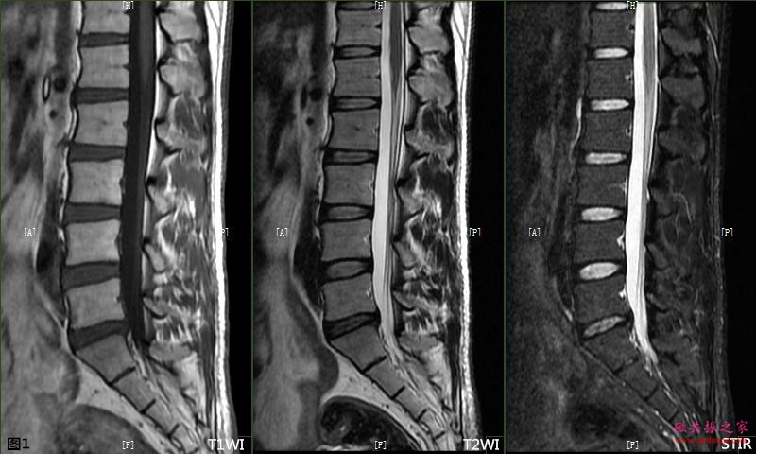

三、IR序列及其应用

2、压脂肪STIR

3、压水FLAIR